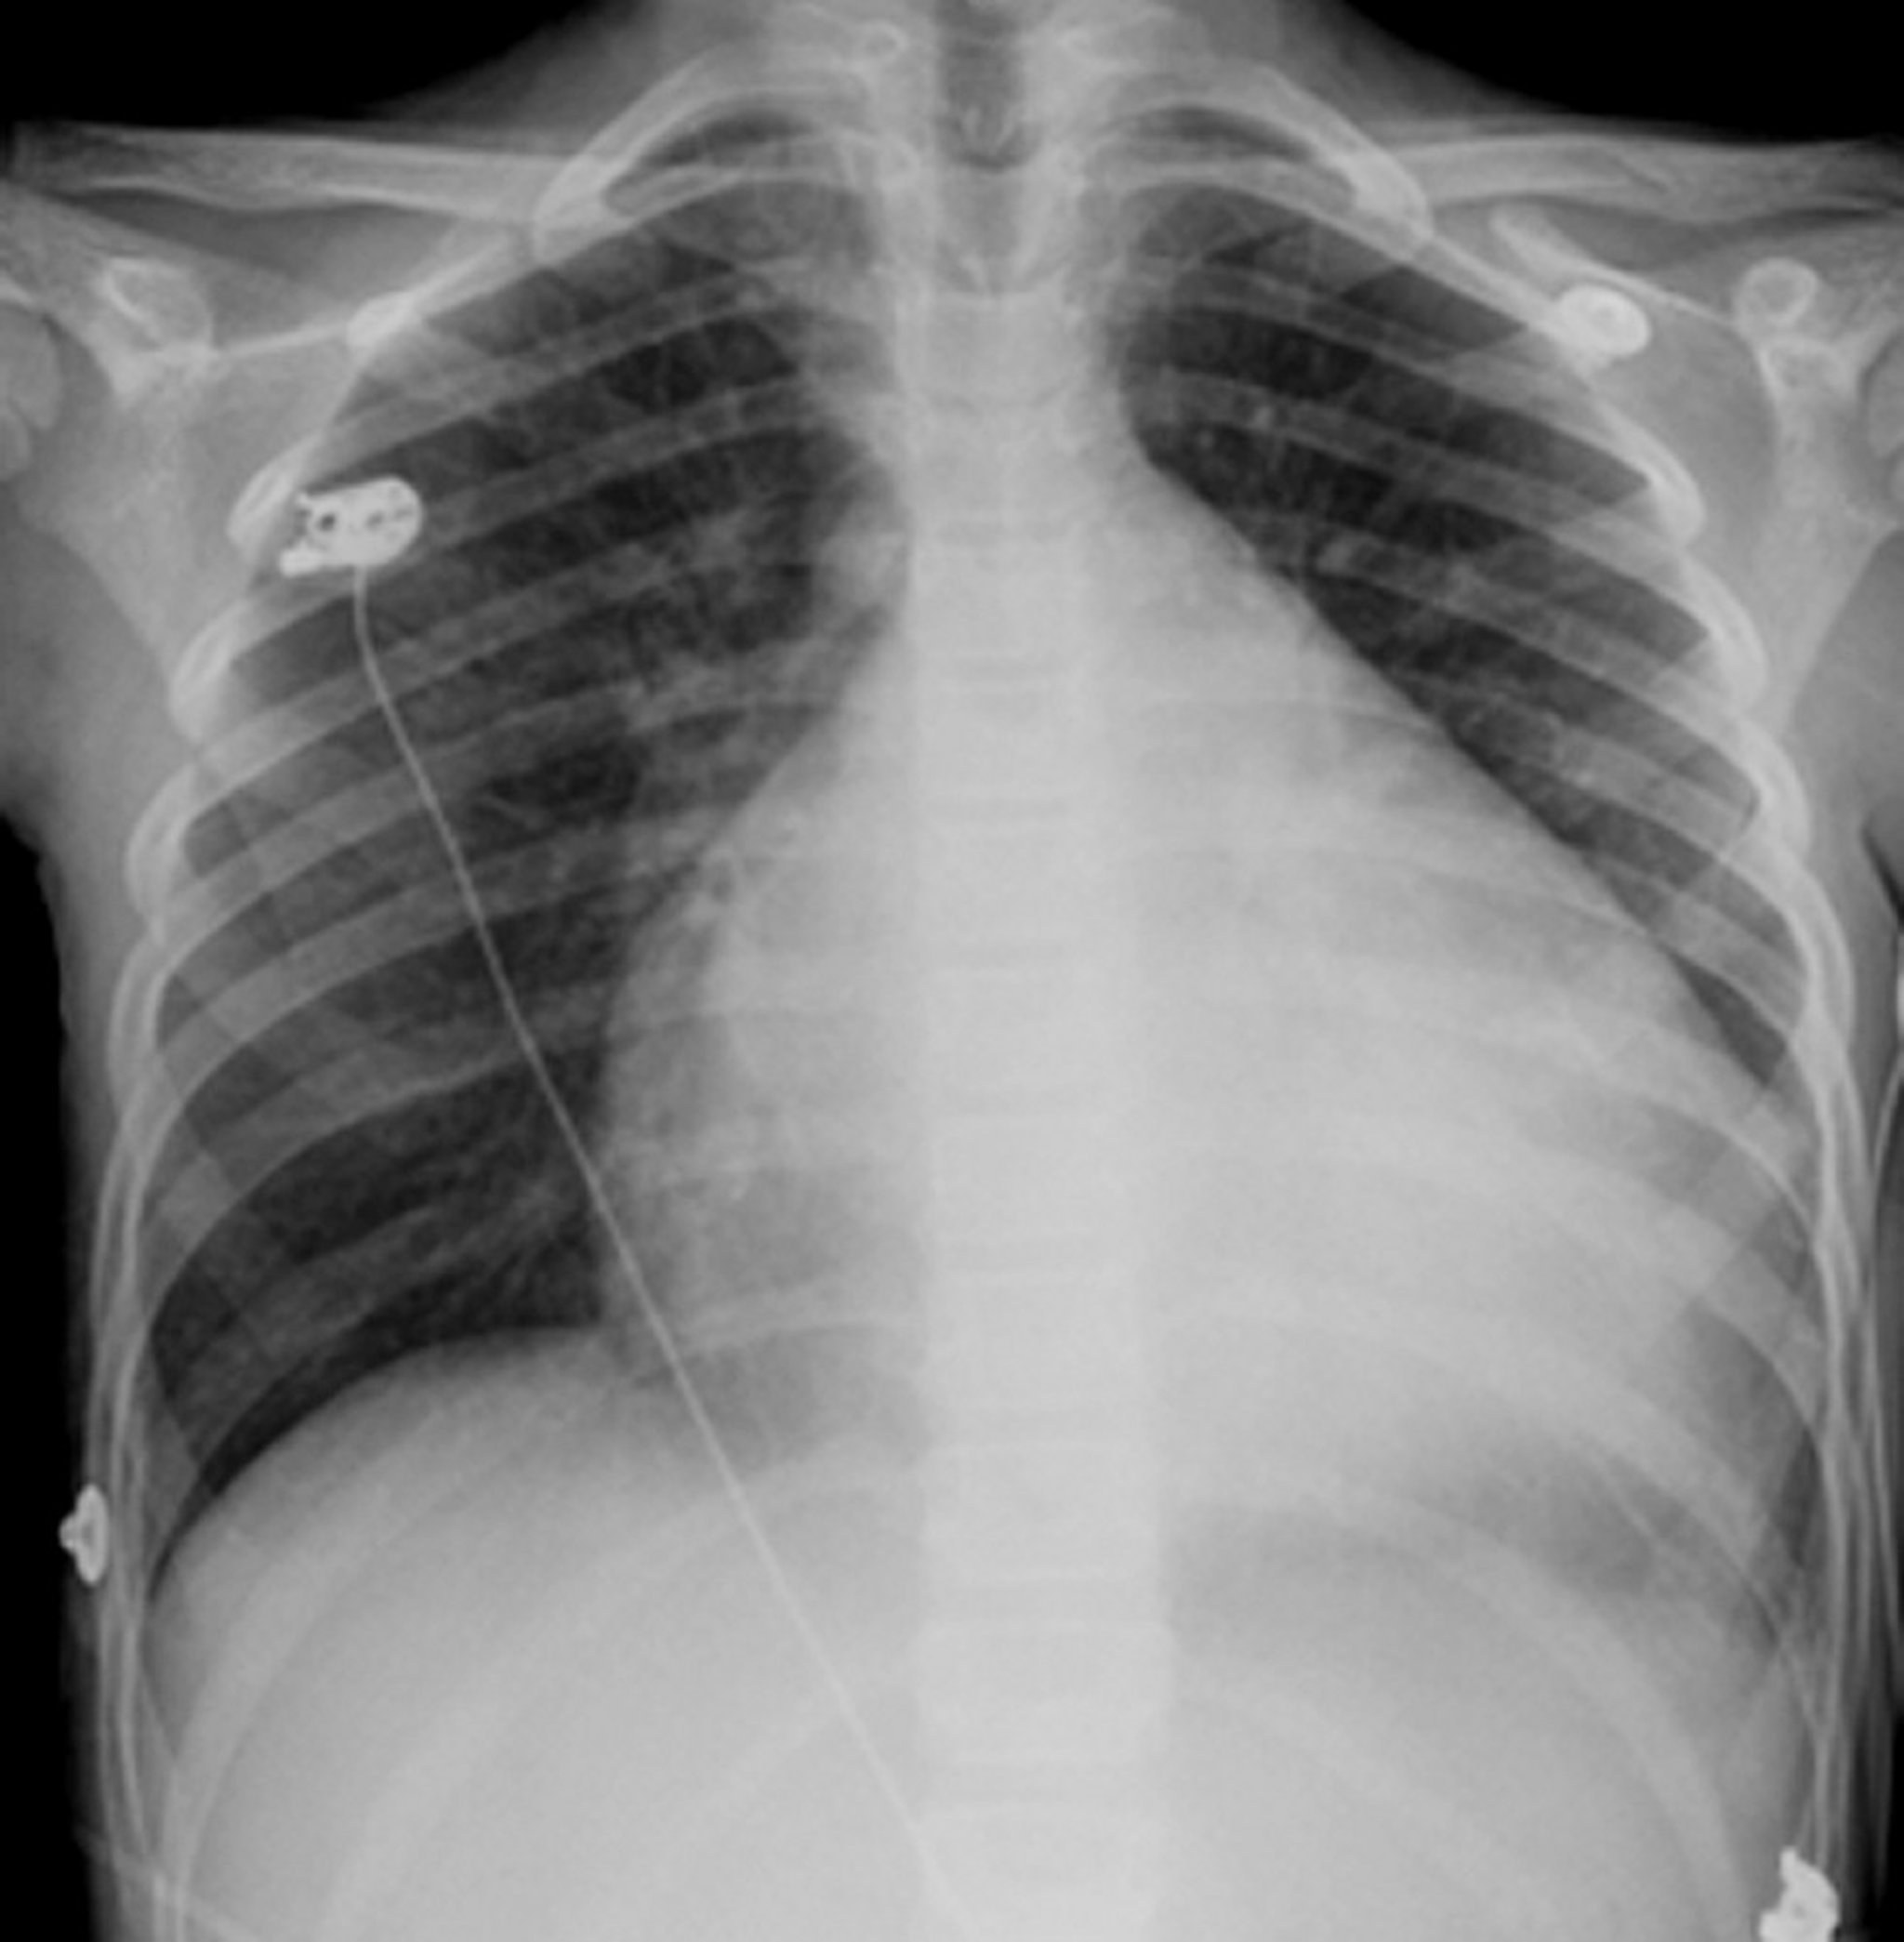

The heart is the globular, white structure in the middle of the chest. Usually it occupies less than half the chest but, in this person who has an enlarged heart (cardiomyopathy), the heart is almost 3/4 the dimension of the chest.